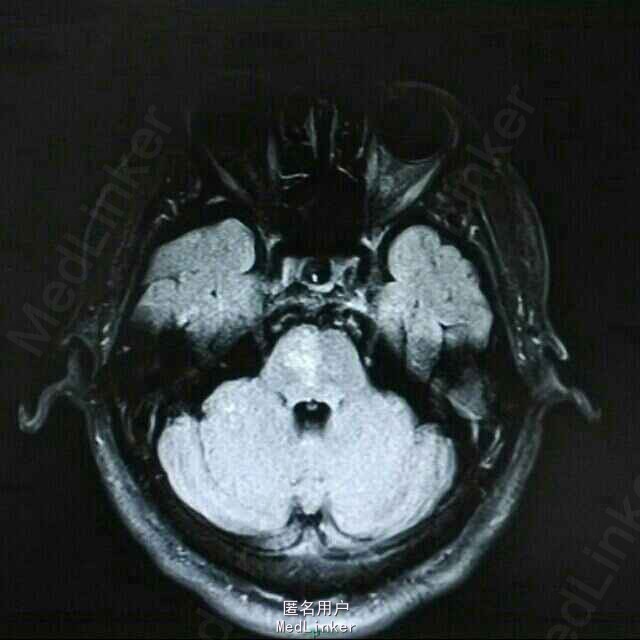

查体:BP 136/84mmHg,抬腿右下肢较左侧差,余无明显异常。 辅检:6-8 D-D 1.87,FIB 7.15,ALT 38,AST 46,GGT 37,LDL-C 4.38,铁蛋白 320,CRP 96.7,ESR 70,尿酮体1+ 6-15 PLT 469,ALT 53,GGT 50,ESR 38,D-D 0.59 血糖监测:早餐后高 彩超多普勒:升主动脉较宽,左室舒张功能减低;双侧颈动脉粥样硬化斑形成。 经颅多普勒:双侧颈内动脉、颈外动脉、左侧颈总动脉血流速度减慢;左侧锁骨下动脉、右侧大脑中动脉、大脑前动脉、左侧颈内动脉虹吸部管腔呈收缩状态;左侧颈内动脉虹吸部管腔重度狭窄;各检查动脉管腔应硬化。 头部MR、脑动脉造影MRA:脑干右侧11*12mm梗塞灶;腔隙性脑梗塞;脑萎缩;双侧额部顶部硬膜下积液;左侧椎动脉起始段及椎动脉-基底动脉汇合段管腔中度狭窄,双侧颈总、颈内外动脉、双侧大脑前中后动脉多发中-重度狭窄,动脉粥样硬化表现。

诊断:脑梗塞;高血压病3级 极高危;糖尿病 2型;动脉粥样硬化;高脂血症;慢性胃炎 治疗:依达拉奉、马来酸桂哌齐特、丹森川穹嗪注射,小牛血清去蛋白注射液;硝苯地平缓释片;阿司匹林肠溶片;阿托伐他丁钙片;阿卡波糖片。